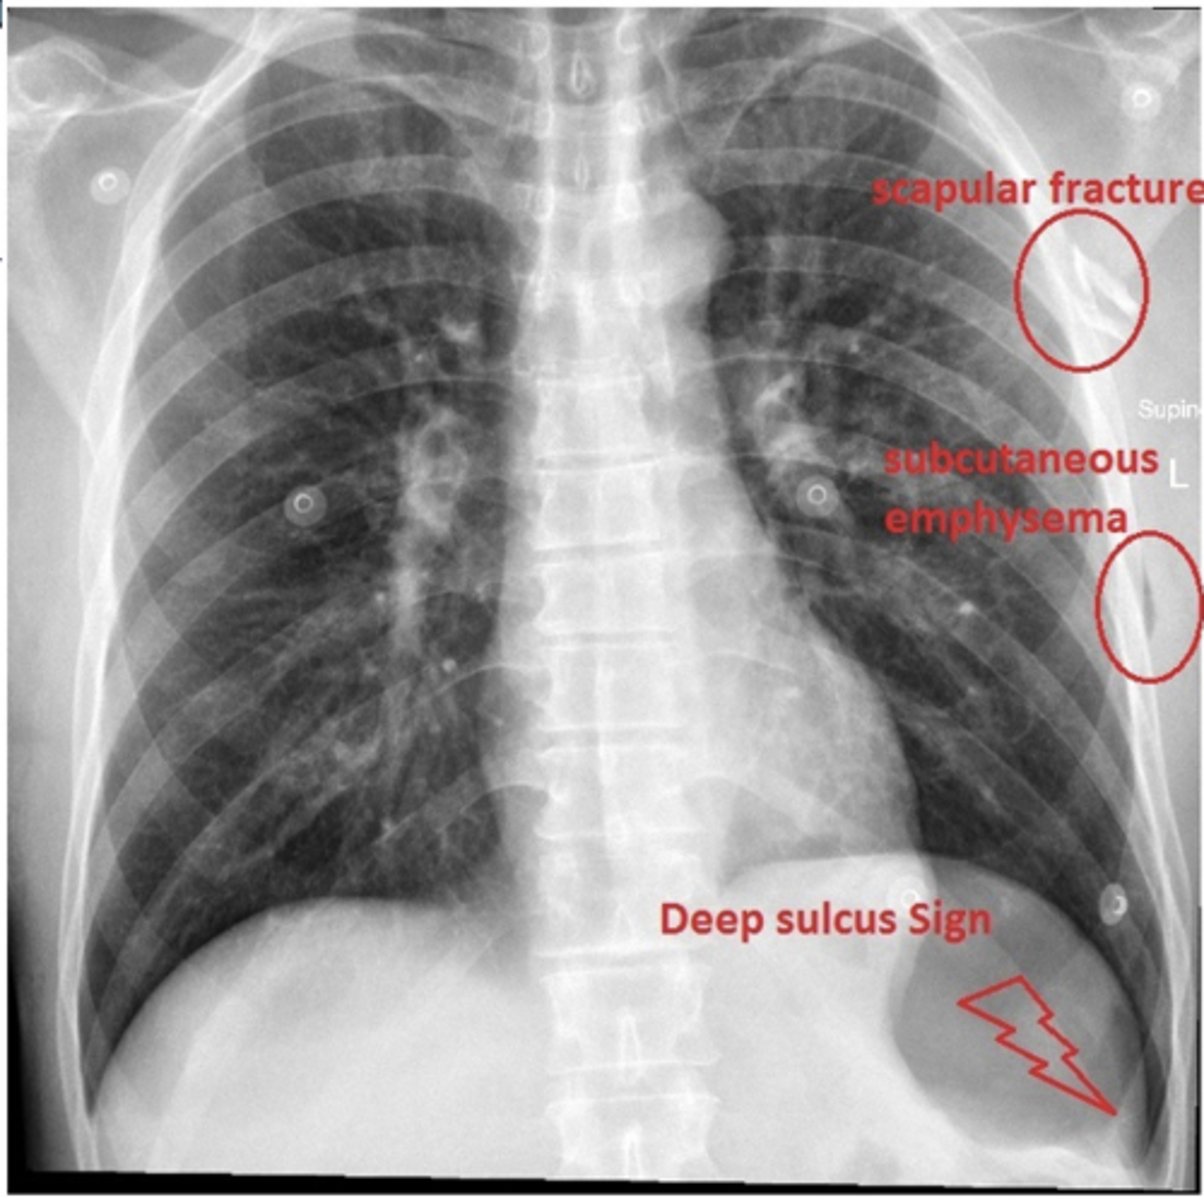

refer to picture

ID findings in red

<p>ID findings in red</p>